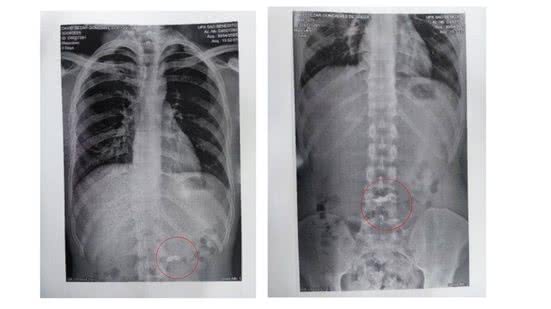

Exame de radiografia identificou o objeto no estômago do homem de 20 anos - Foto: Reprodução/PM-MG

Ainda segundo o boletim de ocorrência, a mulher afirmou que um dos suspeitos havia engolido a correntinha de ouro. O fato foi confirmado depois pela polícia, que localizou o trio em Santa Luzia, na região metropolitana da capital. O exame de radiografia identificou o objeto no estômago do homem de 20 anos.